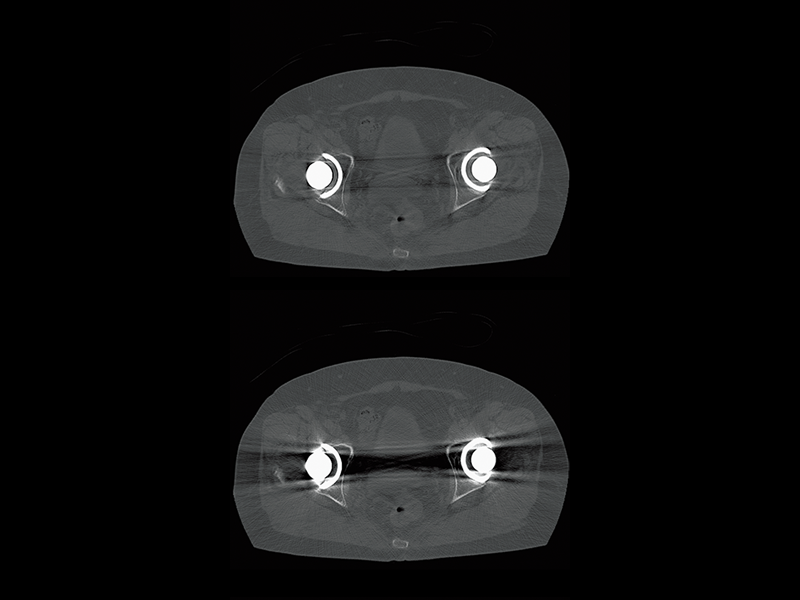

Hip joint(HiMAR Plus)

- * Images other than the axial image were processed by the 3D image analysis system SYNAPSE 3D.